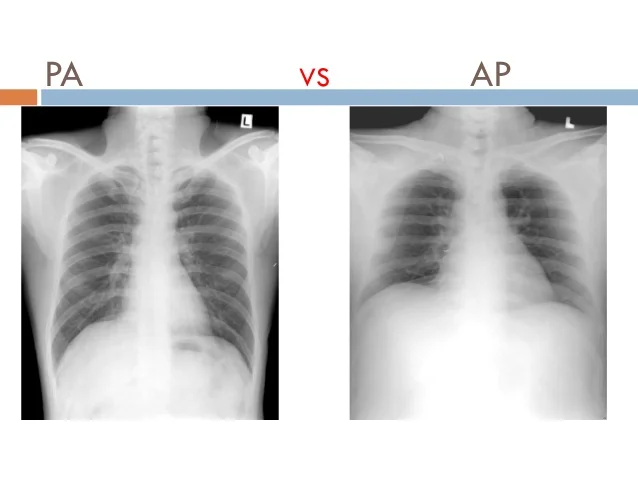

Dwa Znaczniki Rentgenowskie pozwające oznaczyć w jakiej pozycji znajduje się pacjent podczas robienia zdjęcia:

- PA (posterior-anterior) – tylno-przednie – promienie rentgenowskie przenikają przez plecy;

- AP (anterior-posterior) – przednio-tylne – promienie rentgenowskie przenikają przez przednią część klatki piersiowej w stronę pleców.

Przyklad zastosowania:

Zdjęcia rentgenowskie płuc robione są z reguły od strony PA. Dlatego też, gdy zdjęcie płuc jest zrobione AP to pacjent znajduje się w pozycji leżącej, co może z kolei oznaczać stan danego pacjenta (ciężko chory, słaby itp).